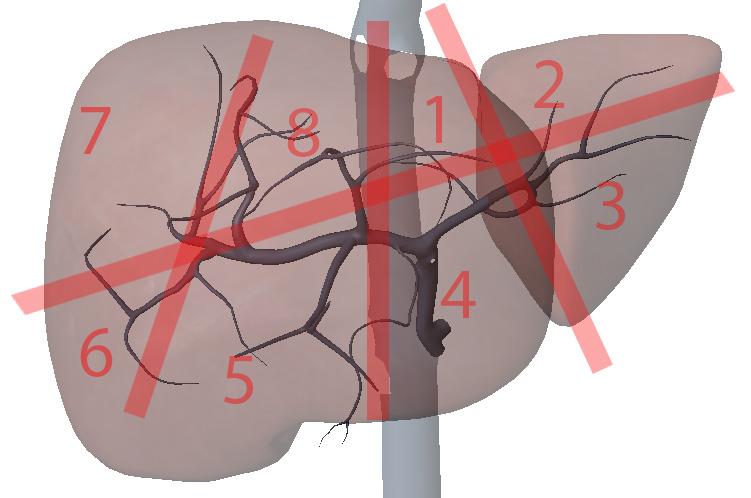

What are the hepatic veins key to?

division of the liver longitudinally

What are the portal veins key to?

transverse division of the liver

What is section 1?

Left Medial superior

What is section 2?

Left lateral superior

What is section 3?

Left lateral inferior

What is section 4?

Left medial inferior

What is section 5?

Right anterior inferior

What is section 6?

Right posterior inferior

What is section 7?

Right posterior superior

What is section 8?

Right anterior superior